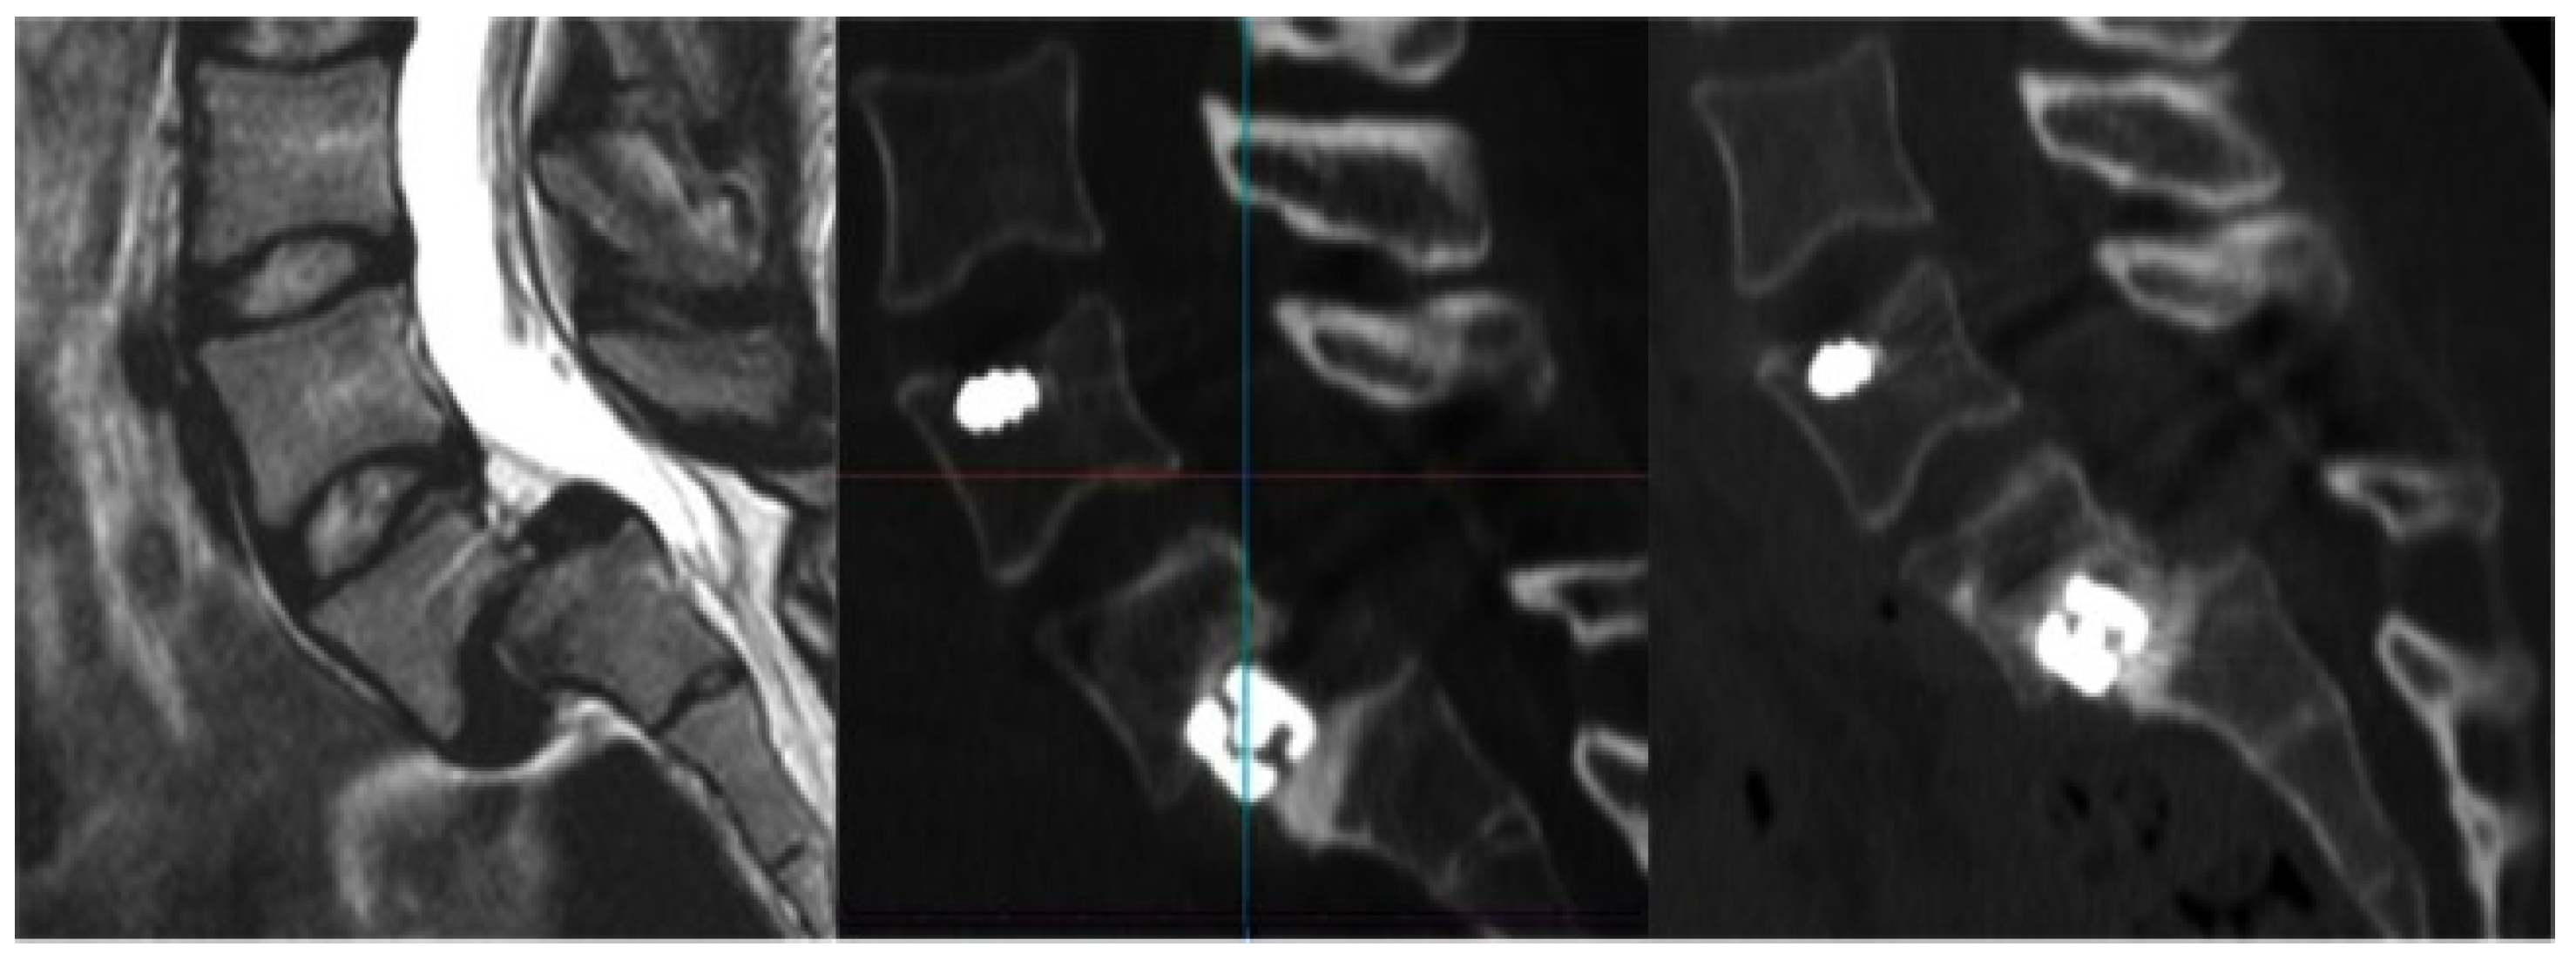

4. Transcervical Approaches

- Wolinsky, J.-P.; Sciubba, D.M.; Suk, I.; Gokaslan, Z.L. Endoscopic Image-Guided Odontoidectomy for Decompression of Basilar Invagination via a Standard Anterior Cervical Approach. J. Neurosurg. Spine 2007, 6, 184–191. [Google Scholar] [CrossRef] [PubMed]

- Ruetten, S.; Hahn, P.; Oezdemir, S.; Baraliakos, X.; Merk, H.; Godolias, G.; Komp, M. Full-Endoscopic Uniportal Odontoidectomy and Decompression of the Anterior Cervicomedullary Junction Using the Retropharyngeal Approach. Spine 2018, 43, E911–E918. [Google Scholar] [CrossRef]

- Ye, J.; Liu, B.; Li, J.; Zheng, G.; Duan, K.; Gao, L.; Zhang, C.; Huang, J.; Tang, Y. Full-Endoscopic Uniportal Retropharyngeal Odontoidectomy: A Preliminary Case Report. Front. Surg. 2023, 9, 973064. [Google Scholar] [CrossRef] [PubMed]